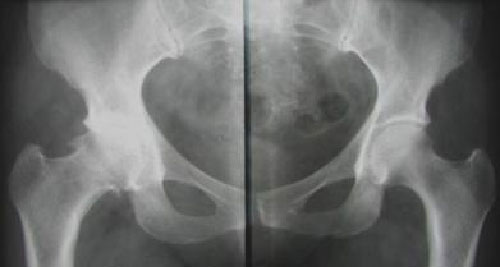

Причины развития артрозов разнообразны. Заболевание может развиваться вследствие перенесённых травм, врожденных (дисплазий) или приобретённых, даже небольших изменений скелета, перенесённых инфекций, инволютивных процессов и ряда других факторов. В основе развития заболевания лежит несоответствие между нагрузкой, испытываемой гиалиновым хрящом, и его способностью этой нагрузке сопротивляться. Это несоответствие вызывается либо чрезмерной нагрузкой на хрящ (при избыточной массе тела, особенностях профессиональной деятельности - грузчики, профессиональные спортсмены), либо функциональной неполноценностью самого хряща в связи с поражениями синовиальной оболочки сустава (отвечает за питание гиалинового хряща), нарушением трофики хряща (при некоторых заболеваниях обмена веществ, эндокринных, неврологических и профессиональных болезнях, при которых в патологический процесс вовлекаются суставы). В начале заболевания поражаются обычно крупные опорные суставы: коленные и тазобедренные, - процесс обычно несимметричный. Боли в суставе возникают при чрезмерных на него нагрузках, усиливаются к концу дня. В покое болей нет. В первой стадии болезни сустав внешне неизменён. При прогрессировании заболевания и развитии синовита (воспаление синовиальной оболочки сустава) боль становится постоянной, сустав может быть припухлым, горячим и болезненным при пальпации. В течение заболевания развивается деформация сустава. В отличие от ревматоидного артрита отсутствует утренняя скованность, хотя после продолжительного пребывания в покое возможна некоторая тугоподвижность в суставах. Симптоматика при остеоартрозе нарастает к вечеру, а при ревматоидном артрите максимальная выраженность симптомов - утром. При длительно текущем заболевании развивается некоторое ограничение в подвижности сустава, возможно появление хруста при пассивных движениях.